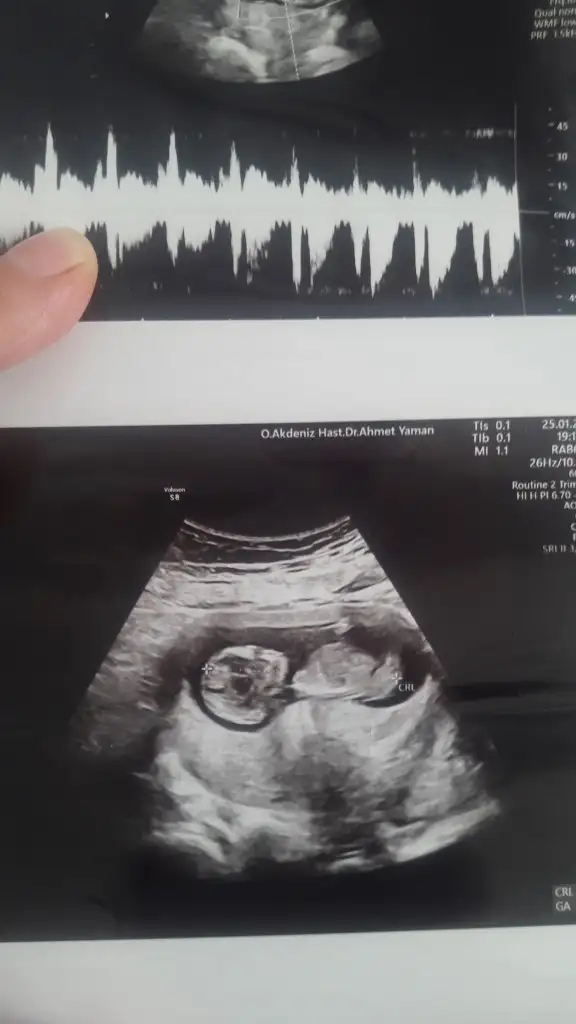

dr soylemeden siz gorun genital nub teorisi ( bebegin cinsiyeti)

11+3 ultrasona gore tahmin eder misin ?

• 20220126_133726.webp

20220126_133726.webp

41,3 KB · Görüntüleme: 57